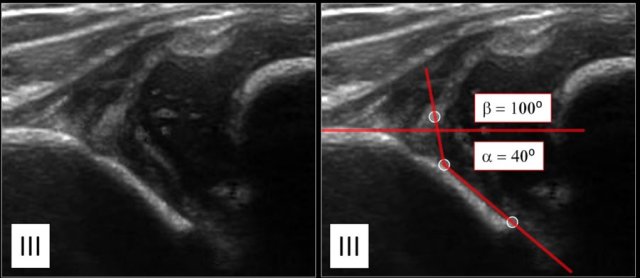

Type III

In type III hips the femoral head dislocated.

The labrum is moved upwards.

The alpha-angle, which is a measurement of the bony roof of the acetabulum, mainly determines the hip type.